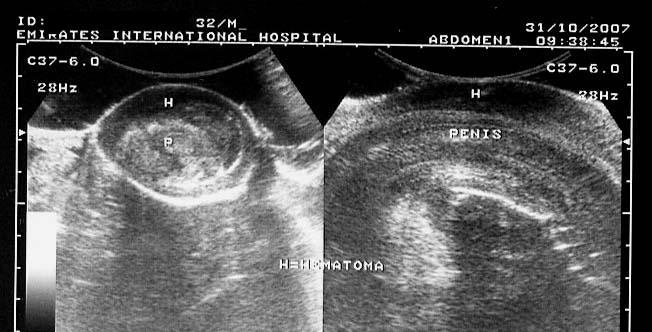

Penile hematoma

The above 3 ultrasound images reveal a hypoechoic collection lateral to the left corpus cavernosum of the penis following penile trauma. Color doppler image reveals a possible source of the hemorrhage. There is evidence of rupture of the lateral aspect of the tunica albuginea of the penis. Images reveal a transverse section of the affected part. Case and images courtesy of Mr. Shlomo Gobi, Israel.